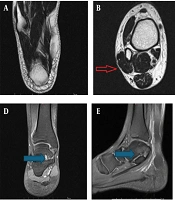

Prediction of Microvascular Invasion in Recurrent Hepatocellular Carcinoma Prior to the Second Surgery Using Enhanced MRI and Variations in Clinical Features